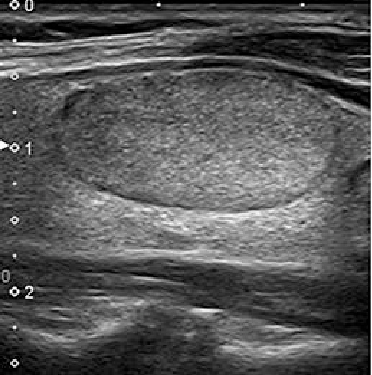

Hipoekoik nodül, normal tiroid dokusundan daha koyu görünen nodülleri ifade eder ve genellikle solid kitle şeklindedir. İyi huylu olabileceği gibi, şüpheli nodüller de olabilir.

Sonuç olarak, ultrasonografide hipoekojenik görünüm tiroid kanseri açısından şüphe uyandırabilir ve dikkatle değerlendirilmelidir. Kesin tanı için ince iğne aspirasyon biyopsisi gerekebilir.